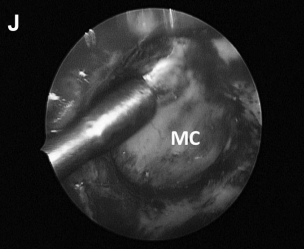

▼(G)切除病变后,术中可见内侧的后颅窝硬脑膜,外侧为Meckel 腔 (MC) 和半月神经节。可用肌电图监测探头监测三叉神经的运动功能状态。